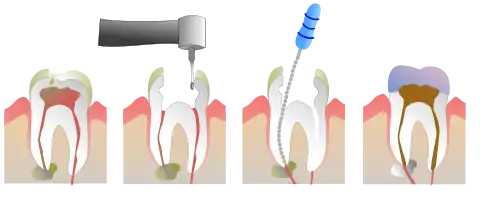

Root canal treatment (also known as endodontic therapy, endodontic treatment, or root canal therapy) is a treatment sequence for the infected pulp of a tooth that is intended to result in the elimination of infection and the protection of the decontaminated tooth from future microbial invasion. It is generally done when the cavity is too big for a normal filling.[1] Root canals, and their associated pulp chamber, are the physical hollows within a tooth that are naturally inhabited by nerve tissue, blood vessels and other cellular entities.[2]

Endodontic therapy involves the removal of these structures, disinfection and the subsequent shaping, cleaning, and decontamination of the hollows with small files and irrigating solutions, and the obturation (filling) of the decontaminated canals. Filling of the cleaned and decontaminated canals is done with an inert filling such as gutta-percha and typically a zinc oxide eugenol-based cement.[3] Epoxy resin is employed to bind gutta-percha in some root canal procedures.[4] In the past, in the discredited Sargenti method,[5][6] an antiseptic filling material containing paraformaldehyde like N2 was used. Endodontics includes both primary and secondary endodontic treatments as well as periradicular surgery which is generally used for teeth that still have potential for salvage.[7][8]

If a tooth is considered so threatened (because of decay, cracking, etc.) that future infection is considered very likely or inevitable, a pulpectomy (removal of the pulp tissue) is advisable to prevent such infection. Usually, some inflammation and/or infection is already present within and/or below the tooth. To cure the infection and save the tooth, the dentist drills into the pulp chamber and removes the infected pulp. To eliminate bacteria from the pulp chamber and root canals, the use of efficient antiseptics and disinfectants is necessary.[11] The soft tissues are either drilled out of the root canal(s) with engine driven rotary files, or with long needle-shaped hand instruments known as hand files (H files and K files).

The endodontist makes an opening through the enamel and dentin tissues of the tooth, usually using a dental drill fitted with a dental burr.

Removal of pulp tissue

There have been a number of progressive iterations to the mechanical preparation of the root canal for endodontic therapy. The first, referred to as the standardized technique, was developed by Ingle in 1961, and had disadvantages such as the potential for loss of working length and inadvertent ledging, zipping or perforation.[12][13] Subsequent refinements have been numerous, and are usually described as techniques. These include the step-back, circumferential filing, incremental, anticurvature filing, step-down, double flare, crown-down-pressureless, balanced force, canal master, apical box, progressive enlargement, modified double flare, passive stepback, alternated rotary motions, and apical patency techniques.[14]

The step back technique, also known as telescopic or serial root canal preparation, is divided in two phases: in the first, the working length is established and then the apical part of the canal is delicately shaped since a size 25 K-file reaches the working length; in the second, the remaining canal is prepared with manual or rotating instrumentation.[15] This procedure, however, has some disadvantages, such as the potential for inadvertent apical transportation. Incorrect instrumentation length can occur, which can be addressed by the modified step back. Obstructing debris can be dealt with by the passive step back technique.[16] The crown down is a procedure in which the dentist prepares the canal beginning from the coronal part after exploring the patency of the whole canal with the master apical file.

There is a hybrid procedure combining step back and crown down: after the canal's patency check, the coronal third is prepared with hand or Gates Glidden drills, then the working length is determined and finally the apical portion is shaped using step back techniques. The double flare is a procedure introduced by Fava where the canal is explored using a small file. The canal is prepared in crown down manner using K-files then follows a "step back" preparation with 1 mm increments with increasing file sizes. With early coronal enlargement, also described as "three times technique", apical canals are prepared after a working length assessment using an apex locator; then progressively enlarged with Gates Glidden drills (only coronal and middle third). For the eponymic third time the dentist "arrives at the apex" and, if necessary, prepares the foramen with a size 25 K-file; the last phase is divided in two refining passages: the first with a 1-mm staggered instrument, the second with 0.5-mm staggering. From the early nineties engine-driven instrumentation were gradually introduced including the ProFile system, the Greater Taper files, the ProTaper files, and other systems like Light Speed, Quantec, K-3 rotary, Real World Endo, and the Hero 642.